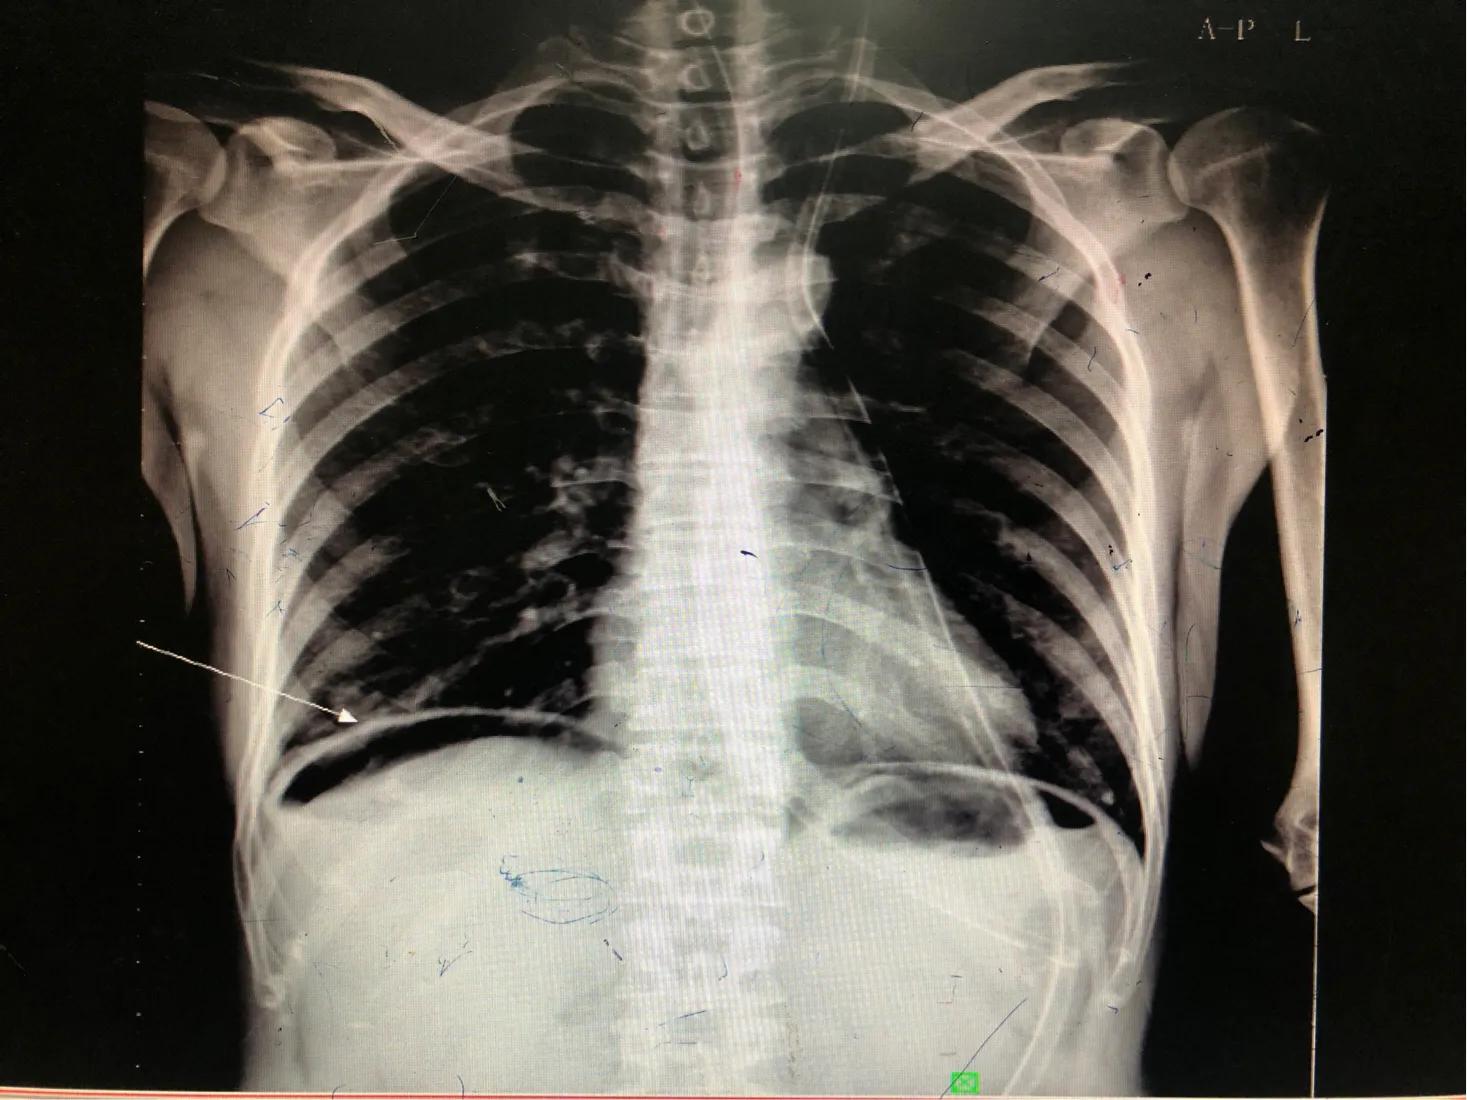

辅助检查:急诊本院DR片符合消化道穿孔X线征,请结合临床。

膈下可见弧形气体影,这就是极可能穿孔的影像学表现。

DR影像学表现:双侧膈面光滑,肋膈角锐利,双侧膈下可见弧形气体影。